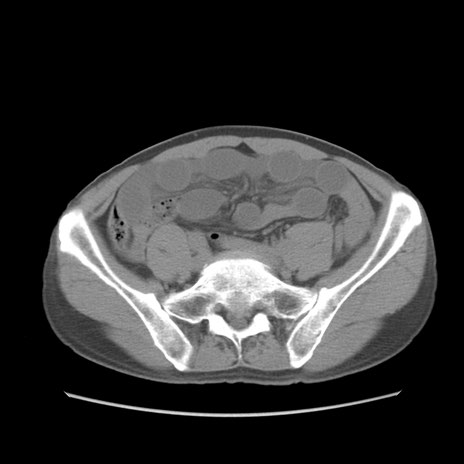

症例56 CT(横断像)

脂肪ウインドウ